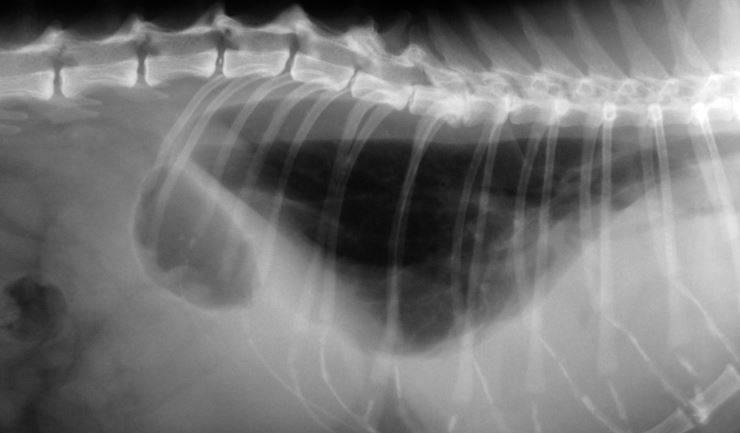

Röntgenfoto’s

Bij de meeste hoestende of benauwde katten moeten er röntgenfoto’s van de borstholte gemaakt worden. Hierop is meestal een verdikking van de wanden van de bronchi te zien, wat leidt tot een versmalling van de luchtwegen. Daarnaast kan ‘air trapping’ (letterlijk ’gevangen lucht’) worden gezien in de luchtwegen. Air trapping treedt op, wanneer ingeademde lucht niet meer uitgeademd kan worden, omdat de luchtwegen zich hebben samengetrokken. Hierdoor raken de longen overvuld met lucht. Het middenrif kan er wat afgeplat uitzien door deze overvulling. Echter, niet alle katten met deze aandoeningen tonen deze afwijkingen. Het röntgenbeeld kan er soms volkomen normaal uitzien.

Met röntgenfoto’s kunnen astma en chronische bronchitis niet definitief vastgesteld worden. Wel kunnen een aantal andere ziekten, die vergelijkbare verschijnselen veroorzaken, uitgesloten worden. Een bijkomend voordeel is dat röntgenfoto’s meestal bij een wakkere kat gemaakt kunnen worden, een roesje is dan niet nodig.